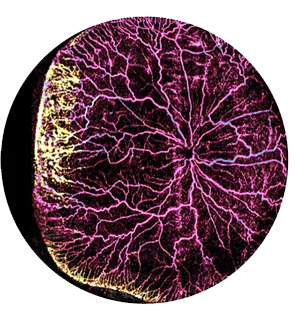

iCam™

Our patented Scanning Laser Ophthalmoscope (SLO) camera is designed to capture high-quality, truly ultra-wide field images of eyes across all ages.